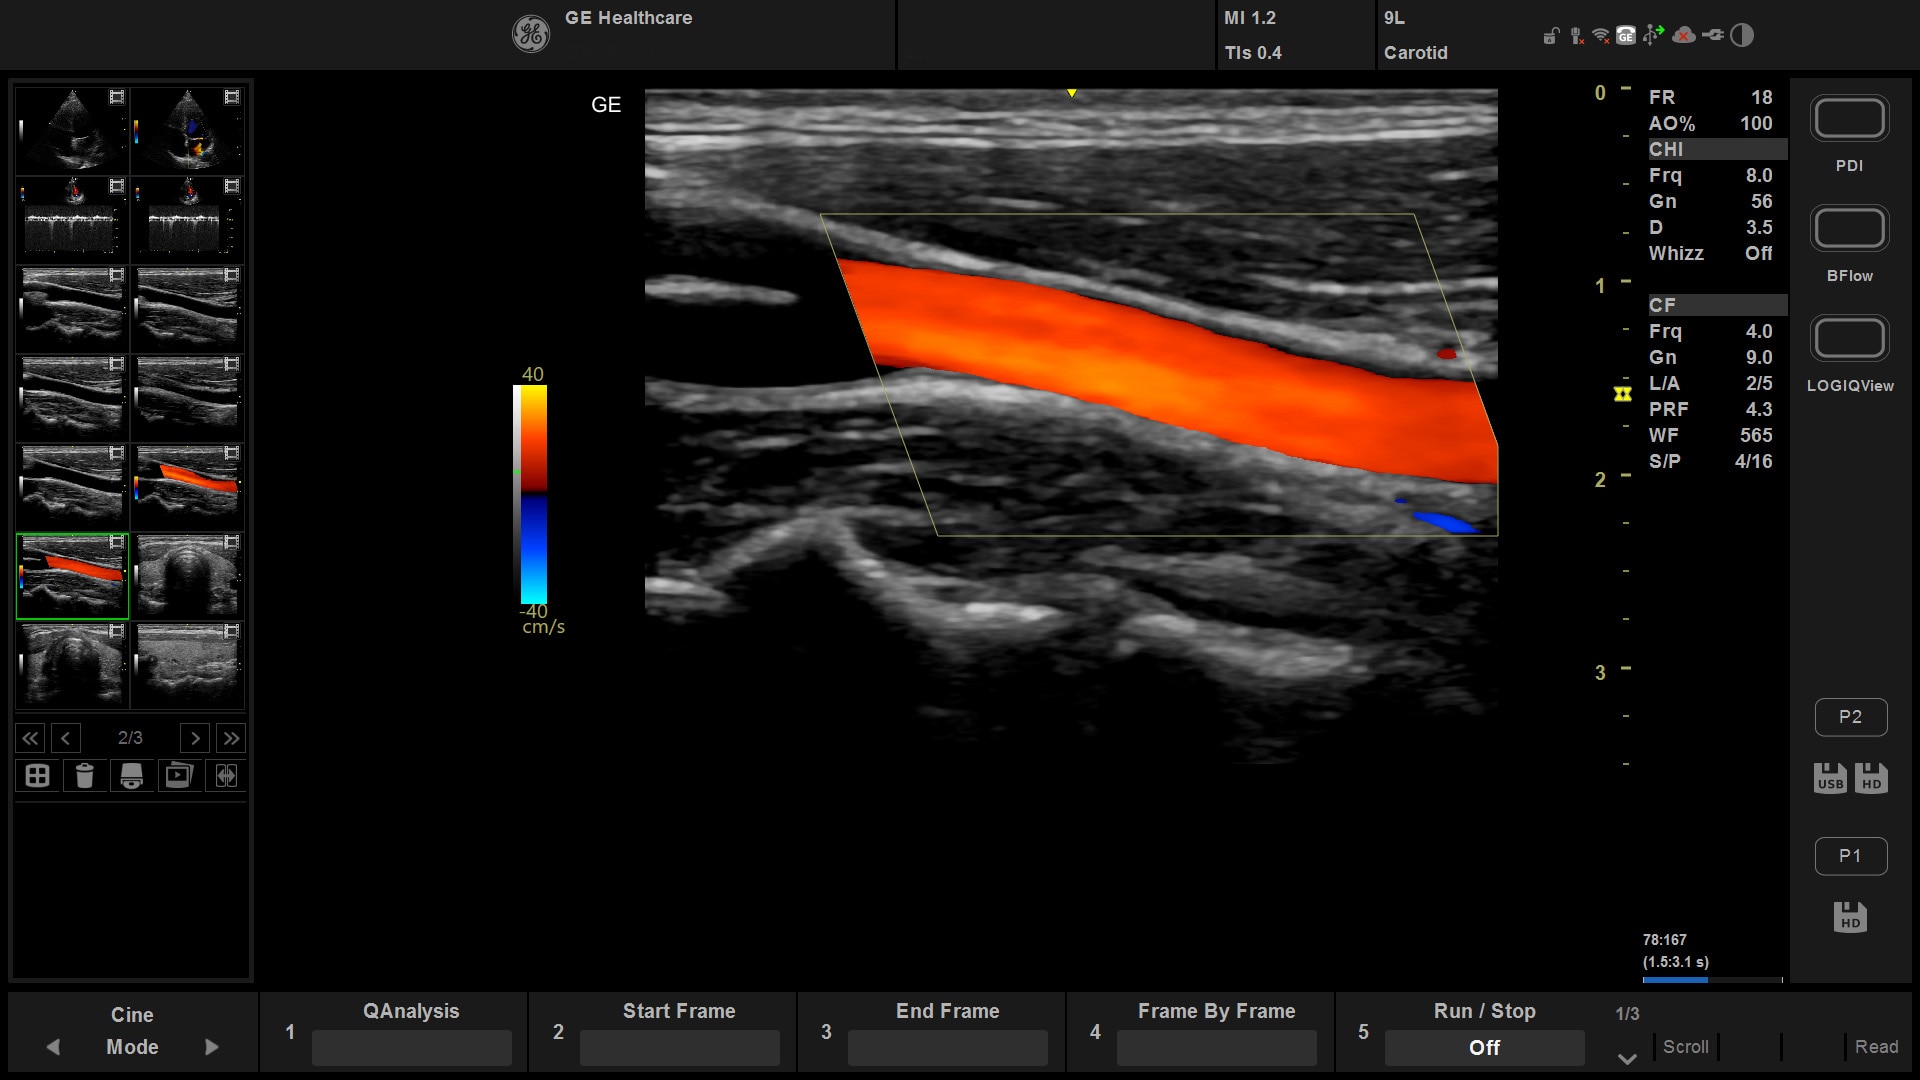

Suited for abdominal, small parts, cardiac, OB/GYN, vascular, and MSK exams

Versana Active features a wide range of advanced clinical applications and automated tools that simplify exams, streamline workflow, and enable fast, high-volume scanning to help you diagnose a wide spectrum of patient conditions.